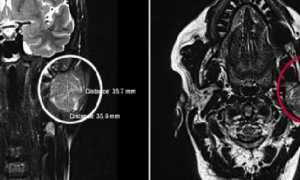

Если у пациента отмечаются симптомы поражения паренхиматозных органов, назначают УЗИ. Метод позволяет изучить структуру органов и их функцию, проверить наличие дополнительных образований.